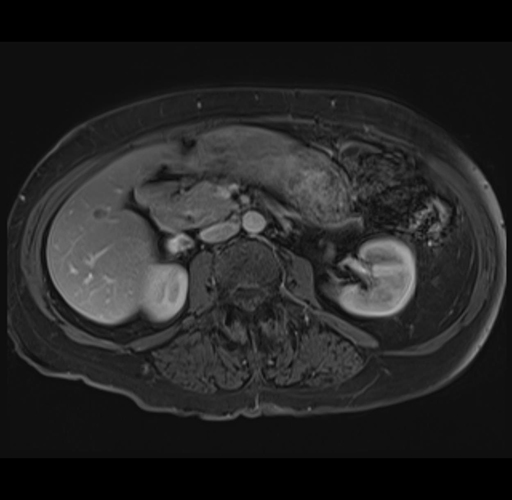

Axial Venous